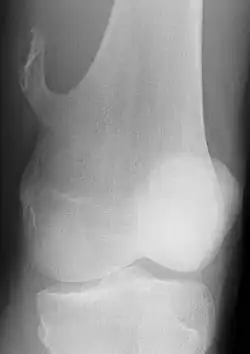

Unter Exostose (von lateinisch ex ‚heraus‘, os ‚Knochen‘ und -ose Krankheit) versteht man eine Knochenwucherung von kompakter Knochensubstanz (Compacta), die über die normale Knochenoberfläche hinausragt (im Volksmund: „Überbein“). Die Exostose gehört zu den Hyperostosen und kann einerseits als hyperplastische Reaktion auftreten, sie wird dann auch als Osteophyt bezeichnet. Eine hyperplastische Reaktion entsteht auf einen Reiz hin, wie beispielsweise Druck auf eine Stelle, die Überbeanspruchung eines Sehnenansatzes oder eine Entzündung der Knochenhaut. Eine Exostose kann als gutartiger Tumor als Osteom entstehen, wobei meist eine langsame Wachstumstendenz besteht. Eine Exostose kann an allen Knochen entstehen und ist entweder symptomlos oder von Schmerzen, Entzündungszeichen und Bewegungseinschränkungen gekennzeichnet. Besonders häufig sind der Mittelfußknochen und der Handrücken betroffen.[1]

- Kartilaginäre Exostosen/Ekchondrome/Osteochondrome (haben einen knorpelig vorgeformten Anteil und bilden sich oft an den Enden langer Knochen, etwa an der Tibia oder am Femur).